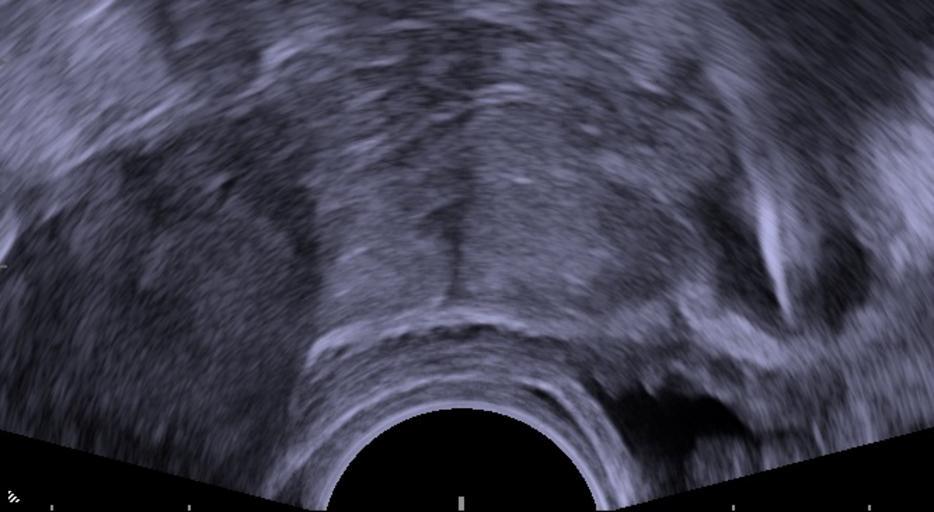

MAKE A MEME View Large Image Perforated IUD.jpg Transvaginal ultrasonography showing an IUD with copper as a hyperechoic rendered as bright line at right 3 centimeters away from the uterus at left The IUD is surrounded by a hypoechoic dark foreign-body granuloma The ...

Keywords: Perforated IUD.jpg Transvaginal ultrasonography showing an IUD with copper as a hyperechoic rendered as bright line at right 3 centimeters away from the uterus at left The IUD is surrounded by a hypoechoic dark foreign-body granuloma The urinary bladder is seen beneath it close the the circular tip of the ultrasound probe at the bottom <P> The patient was a 29 year old woman who had a painful IUD insertion 2 months earlier thumb Follow-up en Projectional radiography plain film radiography of the same case 2014-12-18 own Mikael Häggström other versions cc-zero Uploaded with UploadWizard Vaginal ultrasonography Intrauterine devices